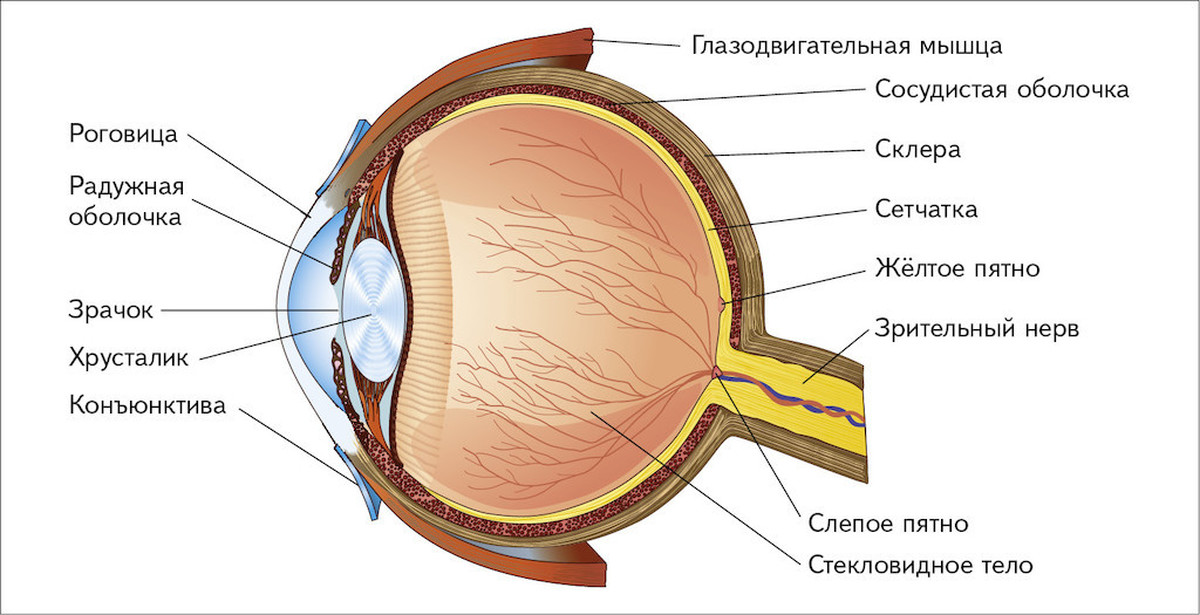

КТ-графики и изображение строения глаза